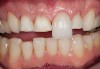

Figure 11  Preoperative photograph of a case in which the patient refused surgery and orthodontics. The treatment goal was to do minimal preparation and use a tough material due to the general medium-to-high risk in every area; obtaining a seal was possible

Figure 11

Figure 12  Postoperative photograph with bonded full-contour restorations in place on the posterior teeth and incisally layered anterior teeth.

Figure 12